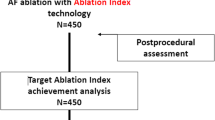

The Ablation Index Registry is a multicenter study that included patients with paroxysmal/persistent atrial fibrillation (AF) who underwent first-time ablation. Each operator performed the ablation using his preferred ablation catheter (ThermoCool® SmartTouch or Surround Flow) and AI setting (380 posterior-500 anterior and 330 posterior-450 anterior). We divided the study population into two groups according to the AI setting used: group 1 (330–450) and group 2 (380–500). Incidence of acute PVR was validated within 30 min after PVI, whereas the incidence of late PVR was evaluated at repeat procedure.

The Ablation Index Registry (AIR) (ClinicalTrials.gov Identifier: NCT03277976) is a prospective, multicenter, research study designed to evaluate the acute achievement of PV isolation with ThermoCool SmartTouch (ST) (Biosense-Webster, Diamond Bar, California) or ThermoCool SmartTouch SF (STSF) (Biosense-Webster, Diamond Bar, California) catheter using the AI Module. Enrollment started in November 2017 and ended in July 2018. The study was approved by local Ethics Committees and complied with the Declaration of Helsinki guidelines. Written informed consent was obtained from all patients.

2.1 Study population and ablation protocol

Enrollment criteria and ablation protocol has been already described [7]. Briefly, we enrolled patients with paroxysmal or persistent atrial fibrillation (AF) who underwent their first AF ablation. Each operator performed AF catheter ablation using its own ablation technique as concerning the ablation catheter (ST or STSF) and the AI setting (380 posterior-500 anterior and 330 posterior-450 anterior). No randomization was required nor was there any deviation from the clinical practice of each center and operator. Therefore, the enrolled population was divided into 4 groups: ST 330–450, ST 380–500, STSF 330–450, and STSF 380–500. For the purpose of this analysis on lesion quality, we divided the study population into two groups according to the AI setting used: group 1 (330 for posterior/inferior segments and 450 for anterior/roof segments) and group 2 (380 for posterior/inferior segments and 500 for anterior/roof segments).